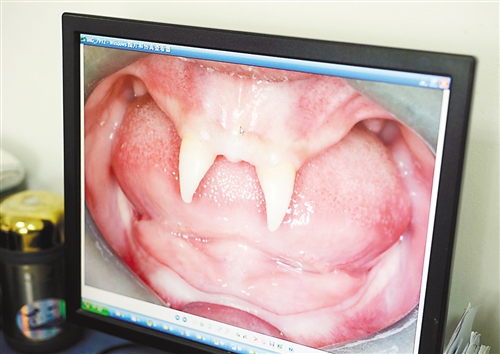

12月18日,16歲的張成(化名)從小到大,只有上顎部分有兩顆牙,看上去更像長(zhǎng)著一對(duì)獠牙。 記者熊明攝

重慶日?qǐng)?bào)訊 每個(gè)人都有牙齒,但對(duì)16歲的張成(化名)來(lái)說(shuō),從小到大,他只有上顎部分有兩顆牙,看上去更像長(zhǎng)著一對(duì)獠牙,這讓他很自卑又易怒。12月18日,在母親的陪同下,他來(lái)到三軍醫(yī)大西南醫(yī)院求助。經(jīng)醫(yī)生檢查,發(fā)現(xiàn)張成患有一種罕見(jiàn)的基因病。

張成是貴州銅仁地區(qū)思南縣人,從生下來(lái)就似乎得了一種怪病,身上毛發(fā)稀少,面部發(fā)育也不好。更奇怪的是,別人家的孩子都長(zhǎng)牙吃東西了,他卻一直長(zhǎng)不出牙齒,最后只在上顎部分冒出兩顆比較突出且對(duì)稱的牙齒,看起來(lái)就像一對(duì)獠牙。